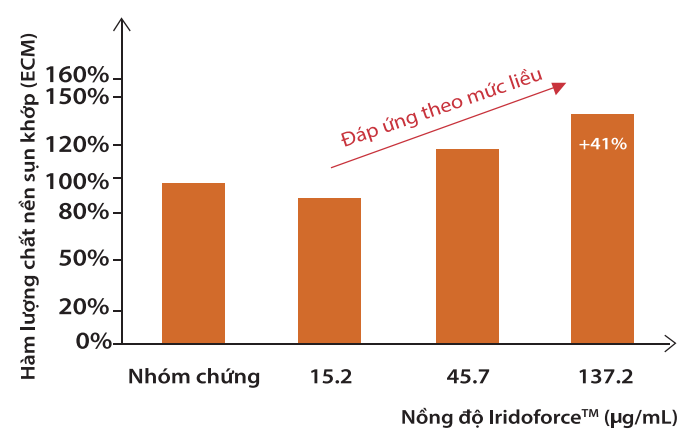

Tin vui là mới đây, các nhà khoa học tại hãng dược phẩm Naturex, Pháp, nghiên cứu thấy rằng: IridoforceTM trong An Kiện Vương – chiết xuất Móng quỷ với hàm lượng hoạt chất harpagosides cao nhất thị trường, giúp tái tạo chất nền sụn khớp từ bên trong hiệu quả, lên đến 41%.

|

| IridoforceTM giúp tăng tái tạo hàm lượng chất nền sụn khớp bên trong cơ thể lên 41% |